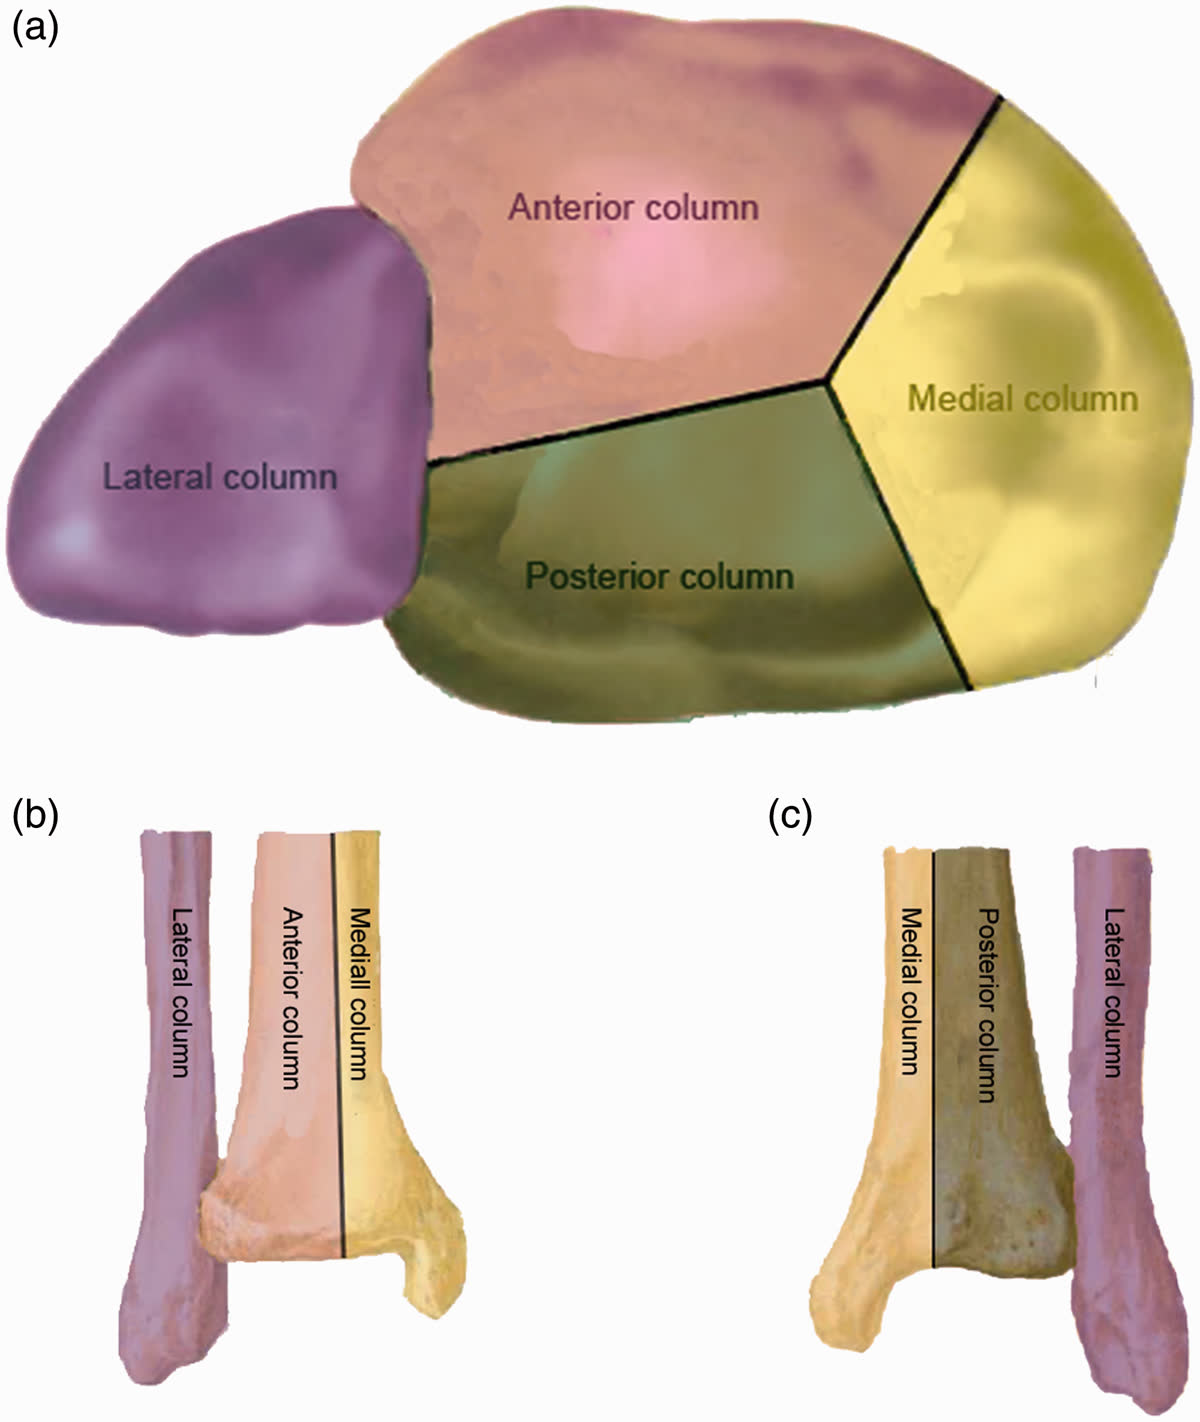

Колонная классификация Topliss (2005)

В оригинальной работе (JBJS Br, 2005) описаны 10 типов переломов, объединённых в 2 семейства, с выделением 6 типичных фрагментов. Упрощённая дидактическая интерпретация разделяет дистальный отдел большеберцовой кости на 3 колонны:

- Переднелатеральная колонна (фрагмент Chaput/Tillaux-Chaput)

- Медиальная колонна

- Заднелатеральная колонна (задняя лодыжка, Volkmann)

Каждая колонна представляет собой независимую суставно-метафизарную единицу, требующую индивидуальной фиксации. Межнаблюдательская надёжность: умеренная [Qiu et al., 2020]. 3D КТ-реконструкция значительно повышает надёжность классификации [Keiler et al., Arch Orthop Trauma Surg, 2020].

Четырёхколонная теория (Chen, 2019)

Расширение классификации Topliss с выделением задней колонны как самостоятельной единицы. По данным Lou et al. (2023), задняя колонна повреждается в 88% переломов пилона (125 из 142) — это наиболее часто повреждаемая колонна. Задние варианты пилона (низкоэнергетические) составляют до 63% всех переломов пилона в некоторых сериях.

Практическое значение: при переломах AO/OTA 43-C не всегда необходима фиксация всех колонн — стабилизация 2–3 ключевых колонн может быть достаточной [Bakan et al., Injury, 2023].

Ни одна классификация изолированно не определяет хирургический доступ. Рекомендуется комбинация: AO/OTA для оценки тяжести + колонная классификация для планирования доступов [Bastias & Lagos, Foot Ankle Clin, 2020].